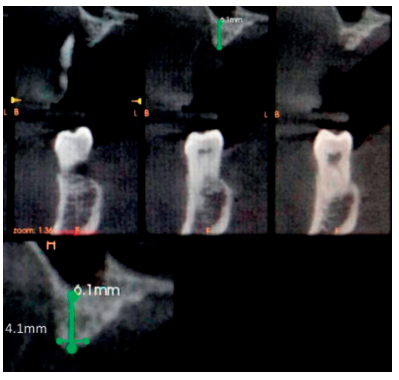

La regeneración localizada de grandes defectos horizontales en los procesos alveolares, previa a la inserción de implantes dentales, sigue siendo un procedimiento quirúrgico desafiante en cirugía bucal. Entre los procedimientos quirúrgicos más utilizados para tal propósito se encuentran la corticotomía con expansión, injerto en bloque “onlay” y la regeneración ósea guiada (ROG), todos ellos con sus diferentes grados de predictibilidad. El uso de micromalla de titanio en combinación con injertos y sustitutos óseos es un método eficiente para la contención, estabilización y protección de estos injertos, permitiendo así una mejor regeneración de los tejidos. Esta técnica no queda exenta de posibles complicaciones asociadas como pueden ser la infección, necrosis del injerto o exposición de la malla de titanio.

Localized regeneration of large horizontal defects in alveolar processes prior to the insertion of dental implants remains a challenging surgical procedure in oral surgery. Among the most widely used surgical procedures for this purpose are expansion corticotomy, onlay block graft and guided bone regeneration all of them with their different degrees of predictability. The use of titanium micromesh in combination with bone grafts and bone substitutes is an efficient method for the containtment, stabilization and protection of these grafts, thus allowing better tissue regeneration. This technique is not exempt from associated complications such as infection, graft necrosis or exposure of the titanium micromesh.

La literatura científica evidencia que la demanda de procedimientos regenerativos en maxilares atróficos oscila entre el 17-35%6 , la incidencia de exposición de la malla de titanio fluctúa en un rango entre el 5-33%, principalmente en pacientes fumadores, mientras que la prevalencia estará ligada a la aparición de infecciones en el área quirúrgica7 .

Uehara S, Kurita H, Shimane T, Sakai H, Kamata T, Teramoto Y, Yamada S. Predictability of staged localized alveolar ridge augmentation using a micro titanium mesh. Oral Maxillofac Surg 2015; 19(4):411-6.